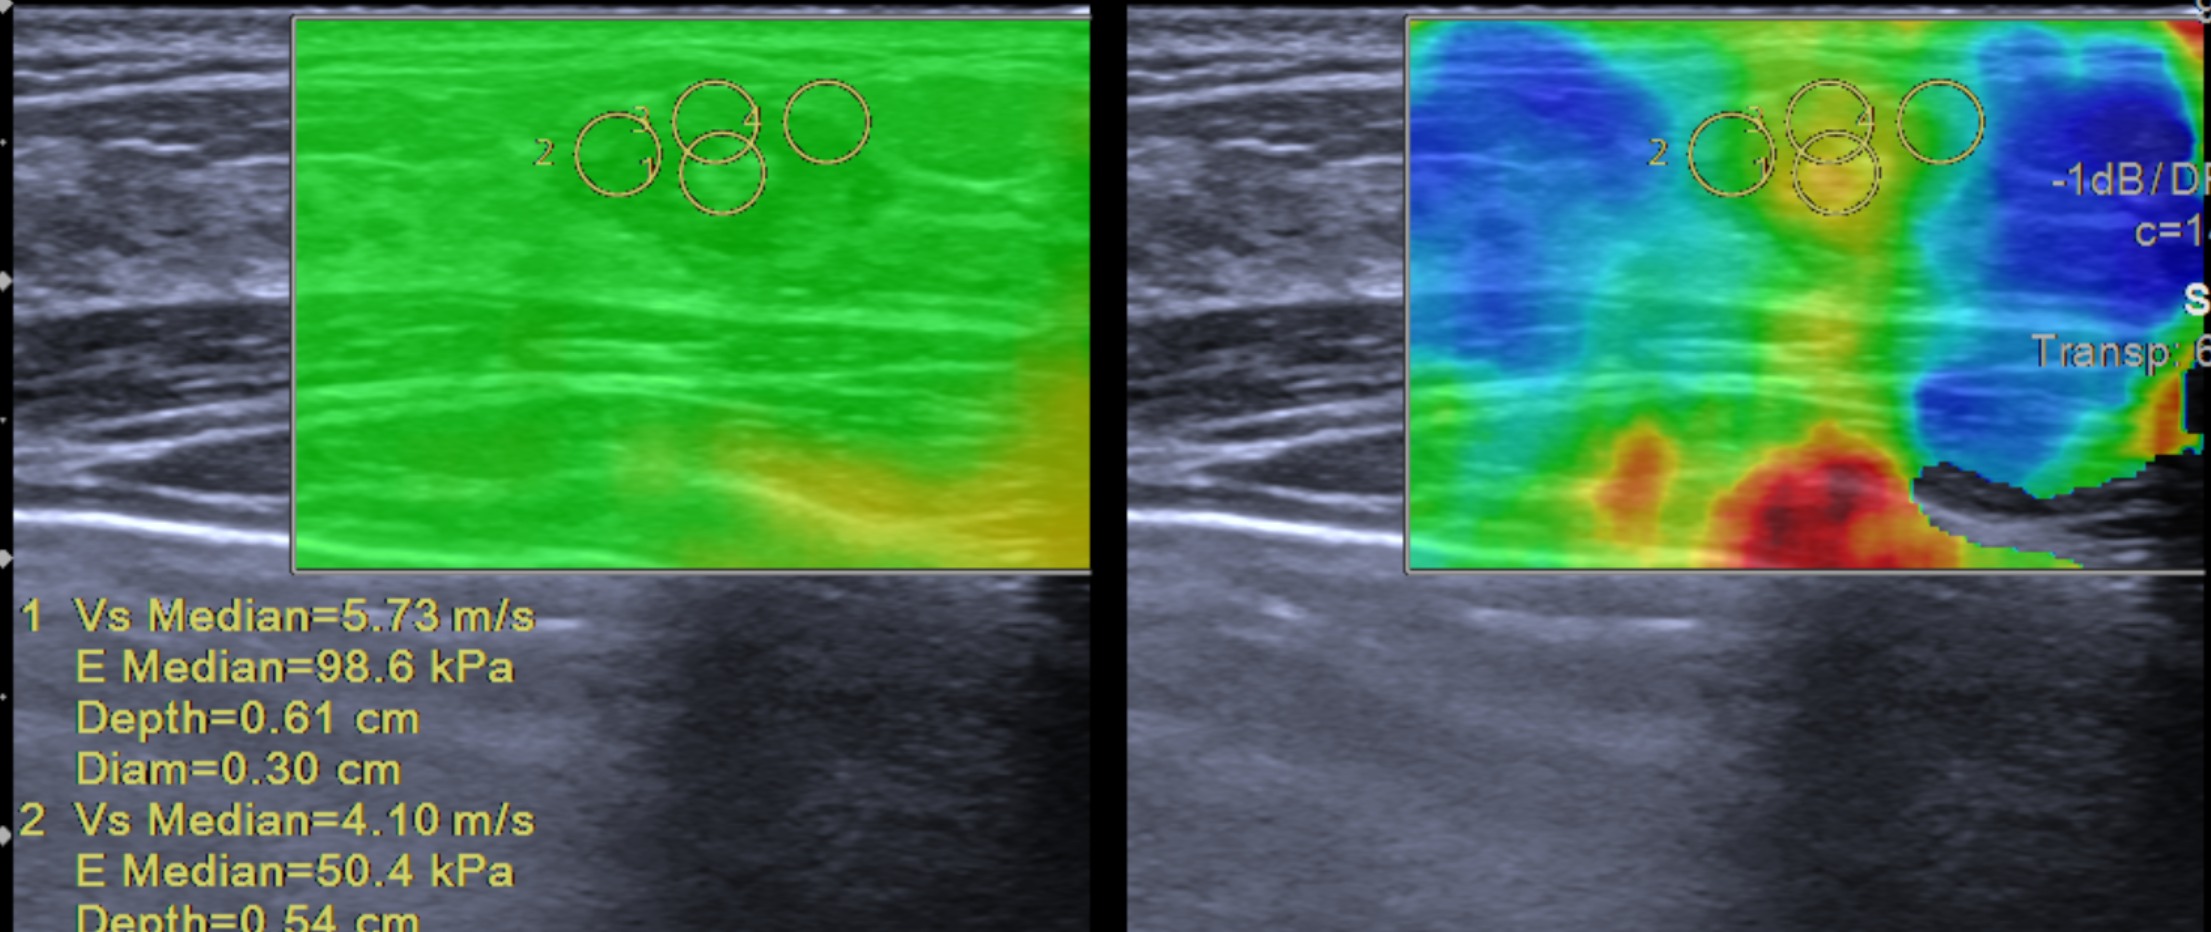

Siêu Âm Đàn Hồi: Phương Pháp Chẩn Đoán Tiên Tiến Cho Ung Thư Vú Tại Mammocare

Siêu âm đàn hồi (elastography) là một phương pháp chẩn đoán hình ảnh tiên tiến, đang được sử dụng rộng rãi tại Mammocare để đánh giá tính đàn...